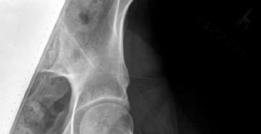

Radiographic and Advanced Imaging

Standard preoperative imaging must include an anteroposterior (AP) pelvis, cross-table lateral, and false-profile view of the affected hip. These evaluate for dysplasia, impingement morphology (cam/pincer), and degenerative changes.

Magnetic Resonance Arthrography (MRA) is the gold standard for evaluating the capsuloligamentous complex. Extravasation of contrast anteriorly often delineates the size and location of the capsular defect. MRA also assesses labral integrity, chondral damage, and the viability of the femoral head. A 3D computed tomography (CT) scan is highly recommended to quantify femoral anteversion and acetabular version, as unrecognized osseous malorientation (e.g., severe femoral retroversion) will predispose the reconstruction to failure if not addressed concurrently with a derotational osteotomy.